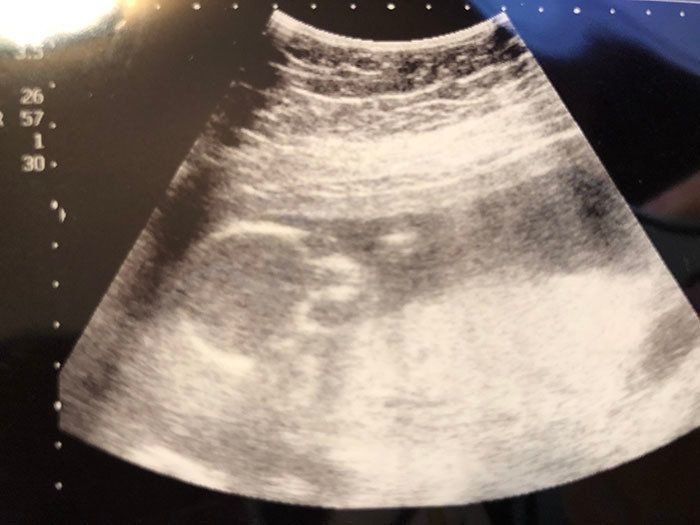

妊娠25週目 胎動が弱い!? 急遽、病院へ

妊娠25週目のある日、胎動が急に弱くなったように感じた私は、不安になり、翌朝病院へ向かいました。しかし、機械を当てると力強い心音が聞こえ、「所見も異状なし」とのこと。この日は日曜日だったので、先生に「お騒がせして…」と謝ると、先生は「赤ちゃんを守れるのはお母さんだけなんだから、大丈夫!」と笑顔で送り出してくれました。私はこの日、赤ちゃんが無事である安堵感と先生の優しさにつつまれ、温かい気持ちで帰宅することができました。